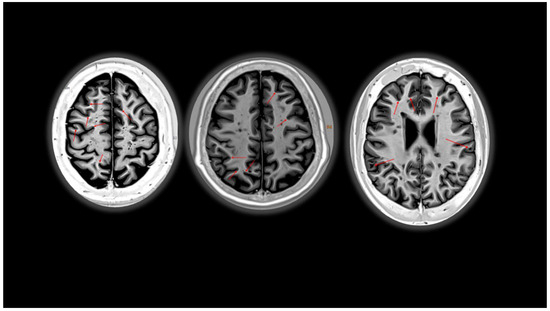

- La Rosa, F.; Abdulkadir, A.; Fartaria, M.J.; Rahmanzadeh, R.; Lu, P.-J.; Galbusera, R.; Barakovic, M.; Thiran, J.-P.; Granziera, C.; Cuadra, M.B. Multiple sclerosis cortical and WM lesion segmentation at 3T MRI: A deep learning method based on FLAIR and MP2RAGE. Neuroimage Clin. 2020, 27, 102335. [Google Scholar] [CrossRef] [PubMed]

- Beck, E.S.; Sati, P.; Sethi, V.; Kober, T.; Dewey, B.; Bhargava, P.; Nair, G.; Cortese, I.C.; Reich, D.S. Improved visualization of cortical lesions in multiple sclerosis using 7T MP2RAGE. Am. J. Neuroradiol. 2018, 39, 459–466. [Google Scholar] [CrossRef] [PubMed]

- Fartaria, M.J.; Sati, P.; Todea, A.; Radue, E.-W.; Rahmanzadeh, R.; O’Brien, K.; Reich, D.S.; Cuadra, M.B.; Kober, T.; Granziera, C. Automated Detection and Segmentation of Multiple Sclerosis Lesions Using Ultra-High-Field MP2RAGE. Investig. Radiol. 2019, 54, 356–364. [Google Scholar] [CrossRef]

- Seewann, A.; Kooi, E.-J.; Roosendaal, S.; Pouwels, P.; Wattjes, M.; van der Valk, P.; Barkhof, F.; Polman, C.; Geurts, J. Postmortem Verification of MS Cortical Lesion Detection with 3D DIR. Neurology 2012, 78, 302–308. [Google Scholar] [CrossRef]

- Kolber, P.; Montag, S.; Fleischer, V.; Luessi, F.; Wilting, J.; Gawehn, J.; Gröger, A.; Zipp, F. Identification of cortical lesions using DIR and FLAIR in early stages of multiple sclerosis. J. Neurol. 2015, 262, 1473–1482. [Google Scholar] [CrossRef] [PubMed]